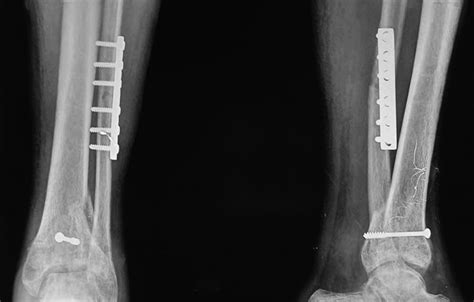

• Open Reduction and Internal Fixation (ORIF): A procedure where the fracture is reduced (realigned) and fixed with plates, screws, or other hardware to stabilize the bone.

Surgical treatment aims to restore the articular surface and provide stability, allowing for early mobilization and rehabilitation.

Post-Operative Care and Rehabilitation